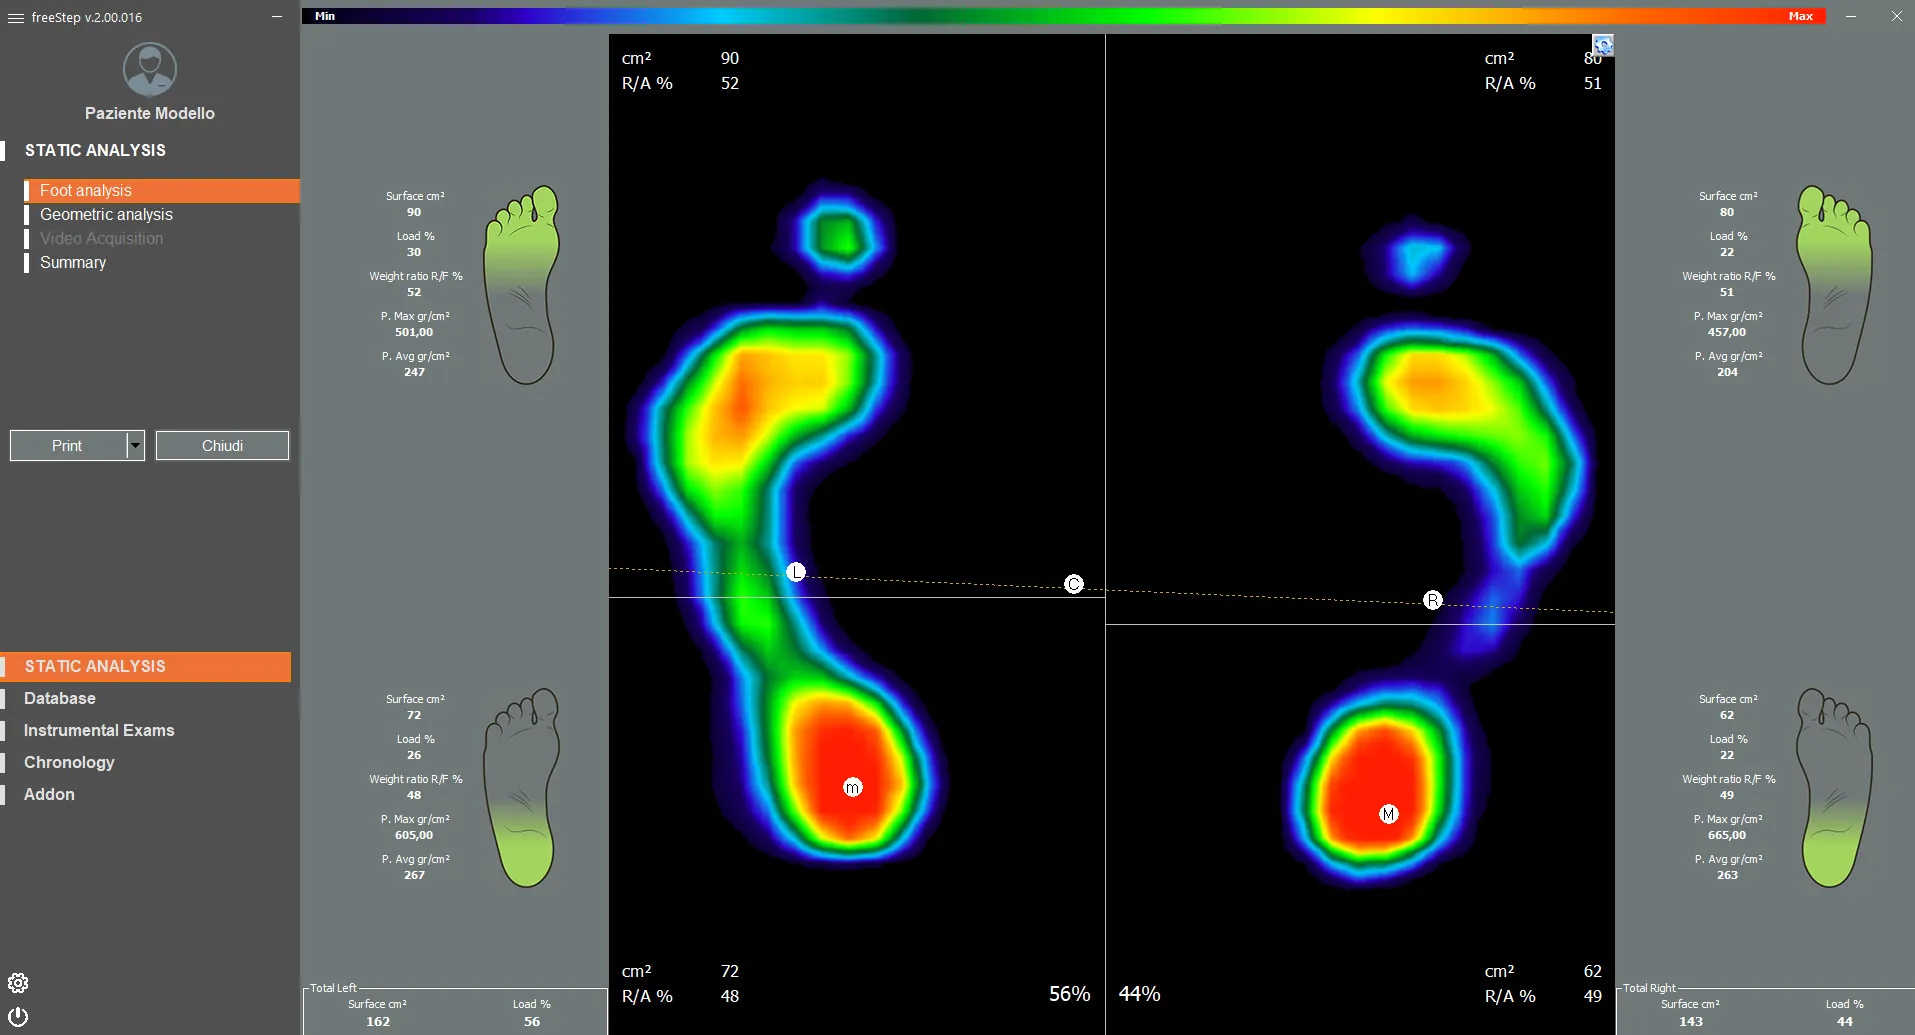

- Поверхности опоры

- Распределение нагрузки

- Оси и углы стопы

- Длина стопы